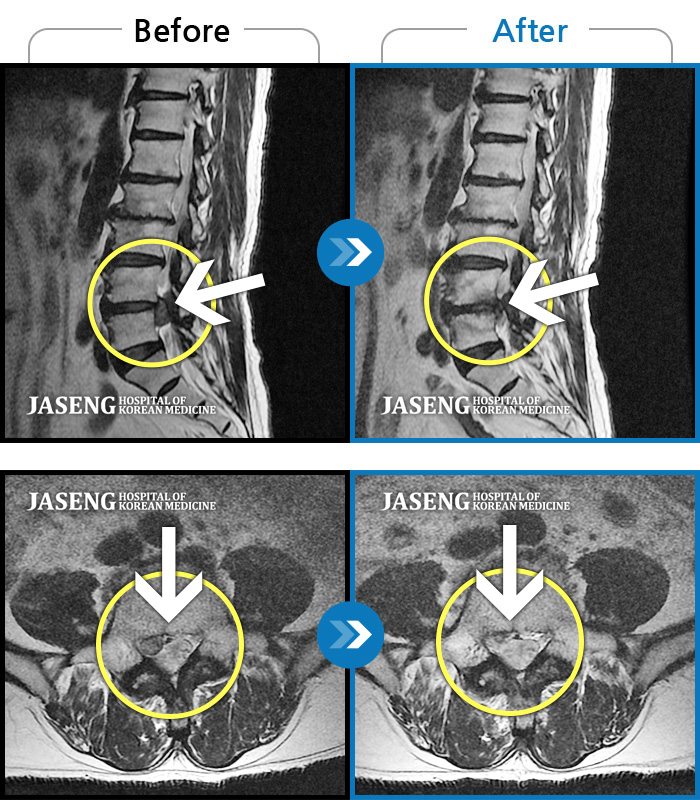

허리디스크

일산 · 김진수 원장

처음 내원 시 허리, 엉덩이가 많이 아프고, 좌측 다리로 근력 및 감각 저하도 있었으며, 야간통을 잠도 못자고 통증 심하여 식사도 무릎꿇고 하는 등 정상적인 활동이 힘든 상태셨습니다.

촬영시기

2022.11.16 ~ 2023.05.24

2023.06.01

조회수 269